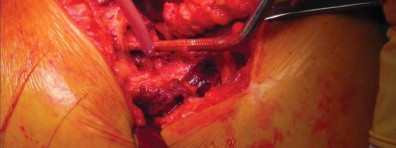

التقنية الجراحية للدكتور محمد هطيف

يستخدم الأستاذ الدكتور محمد هطيف تعديلًا طفيف التوغل للطريقة الجانبية المباشرة (LIDL) لضمان أفضل النتائج لمرضاه. هذه التقنية تضمن دقة عالية مع الحفاظ على الأنسجة.

وضعية المريض والشق الجراحي

يتم وضع المريض في وضع الاستلقاء الجانبي المباشر مع الجانب المراد إجراء الجراحة عليه للأعلى، والحوض عموديًا على الطاولة باستخدام دعامة صلبة. لضمان الاستقرار، يتم وضع دعامات طويلة خلفيًا عند مستوى منتصف الظهر وعند منتصف العجز، وأماميًا عند عظم القص والارتفاق العاني. يتم ثني الورك المقابل حوالي 15 درجة ويتم تبطين الشظية القريبة لمنع الضغط الزائد على العصب الشظوي المشترك. في هذا الوضع، يتم تقدير تقريبي لتساوي طول الساقين عن طريق تقييم مستوى الرضفتين والكعبين. بعد التحضير والتعقيم، يتم تحديد طرف المدور الكبير عن طريق الجس والتقييم عن طريق الجلد باستخدام إبرة نخاع شوكي.

يتم عمل شق مائل من الخلف القريب إلى الأمام البعيد، يتمركز فوق طرف المدور الكبير، ويبلغ طوله حوالي 10-12 سم للرجل متوسط الوزن (70 كجم). يتم تقليل تشريح تحت الجلد لتحديد اللفافة الأساسية إلى الحد الأدنى لمنع تكوين مساحة ميتة.

إدارة الأنسجة الرخوة وخلع رأس الفخذ

تُشق اللفافة العريضة والألياف الأمامية للعضلة الألوية الكبرى التي تتصل باللفافة العريضة قريبًا باستخدام الكي الكهربائي بما يتماشى مع شق الجلد. يتم إزاحة الجراب المدوري خلفيًا للمساعدة في رؤية العضلة الألوية الوسطى والعضلة المتسعة الجانبية. يتم رفع الجزء الأمامي من العضلة الألوية الوسطى عن المدور الكبير باستخدام الكي الكهربائي، ثم يتم تشريحه بشكل غير حاد بما يتماشى مع أليافه بزاوية 45 درجة أمامية-قريبة عند تقاطع الثلثين الأوسط والأمامي للعضلة. يقتصر التشريح على أقل من 3-4 سم باتجاه الرأس من طرف المدور الكبير لتجنب إصابة العصب الألوي العلوي. في غلاف مستمر مع العضلة الألوية الوسطى، يتم رفع الجزء الأمامي من العضلة المتسعة الجانبية عن حافة العضلة المتسعة ويتم شقه بعيدًا بين ثلثيه الأوسط والأمامي. يتم وضع مبعد هومان غير حاد في شق العضلة الألوية الوسطى لسحب الألياف الخلفية وكشف طبقة من الدهون بين المستويات الألوية. تُشق الكبسولة خلف العضلة الألوية الصغرى وعلى طول الجانب العلوي من عنق الفخذ. يقوم المساعد بتباعد وثني وتدوير الطرف خارجيًا لخلع رأس الفخذ.

تحضير الفخذ والحق

يتم تحديد مستوى قطع عنق الفخذ مسبقًا بالتخطيط (باستخدام الأشعة السينية) ومواءمته أثناء الجراحة مع المدور الكبير. بعد قطع عنق الفخذ، يتم تحضير الحُق بالطريقة القياسية قبل تحضير الفخذ. يفضل الأستاذ الدكتور محمد هطيف عادةً وضع الكأس وفقًا للمعالم التشريحية لإعادة إنشاء التوجيه الطبيعي للحُق لدى المريض ويتحقق من الإصدار والميل الصحيحين عن طريق الجس والرؤية المباش